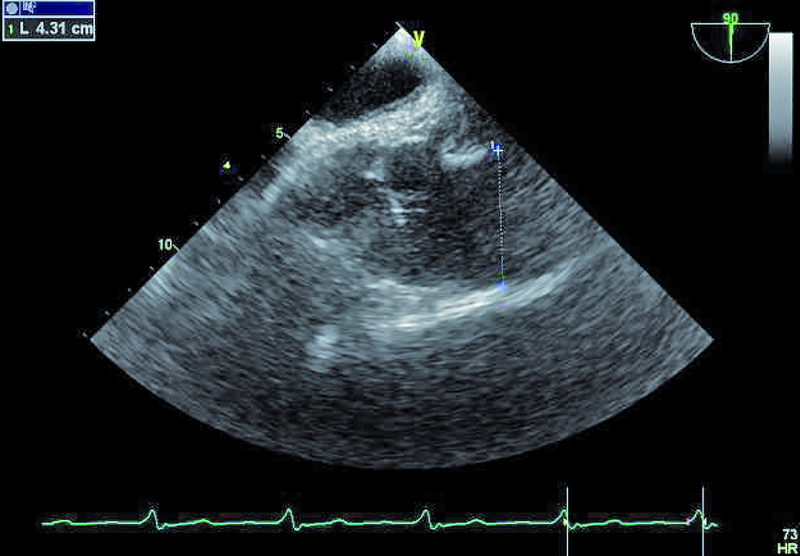

Mężczyzna, lat 25. Jakie patologie można rozpoznać na rycinach?

1. Powiększenie jamy prawej komory (ryc. 1).

2. Dodatkowe echa (skrzepliny, wegetacje?) związane z elektrodą (ryc. 2).